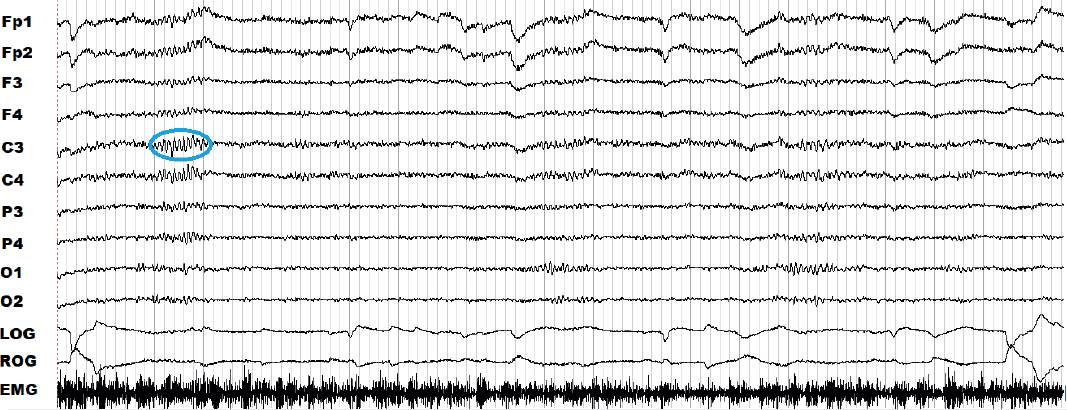

El sueño se clasifica en dos: el sueño de movimientos oculares rápidos (sueño MOR) (Siegel, 2017) y, el de no MOR (sueño NMOR). El sueño NMOR se divide a su vez en etapas 1, 2 y 3 (Ferré y Lainez, 2015). Cuando se está despierto o en el estado de vigilia con ojos cerrados se puede observar un registro en donde predomina un EEG con oscilaciones denominadas “ritmo alfa” y un tono muscular alto (Figura 2). En cambio, cuando el sueño propiamente comienza, es decir, en un registro de la etapa 1 del sueño NMOR, se observan frecuencias mezcladas, hay disminución del ritmo alfa y el tono muscular es menor que en vigilia (Figura 3) (AASM, 2007; Ferré y Lainez, 2015).

Figura 2 Registro de la polisomnografía durante 30 s de la vigilia con ojos cerrados de una paciente del grupo control. Los canales frontopolares (Fp), frontales (F), centrales (C), parietales (P) y occipitales (O) se denotan en la columna de la izquierda; las regiones cerebrales se asocian a números: las derivaciones del lado derecho de la cabeza se representan con números pares y las del lado izquierdo de la cabeza, con los nones. Los electrooculogramas (EOG) derecho e izquierdo son LOG y ROG, por sus siglas en inglés; el canal de la electromiografía (EMG) comprende el trazo grueso. En azul se observa el ritmo alfa característico de este estado.